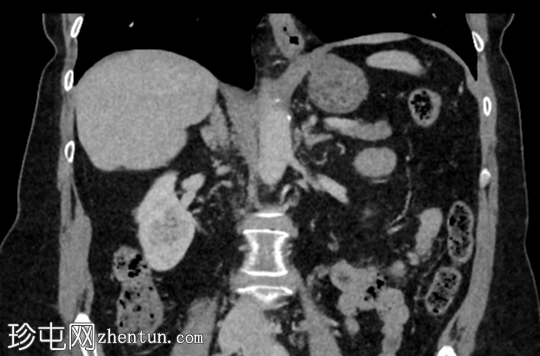

已知乳腺癌病例,随访CT扫描中偶然发现右肾外生性病变。

年龄:65岁

性别:女

轴位

平扫

右肾后上极可见2.8 cm外生性强化病灶,提示肾细胞癌(RCC)。右肾静脉和下腔静脉通畅。未见明显局部淋巴结肿大。右肝叶可见高密度金属影。可见含脂肪的脐疝。

右肾部分切除术后病理检查显示为嫌色细胞肾细胞癌。